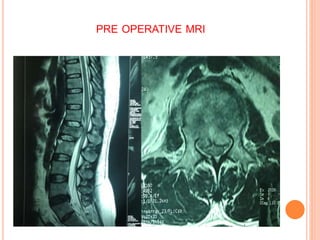

PRE OPERATIVE MRI